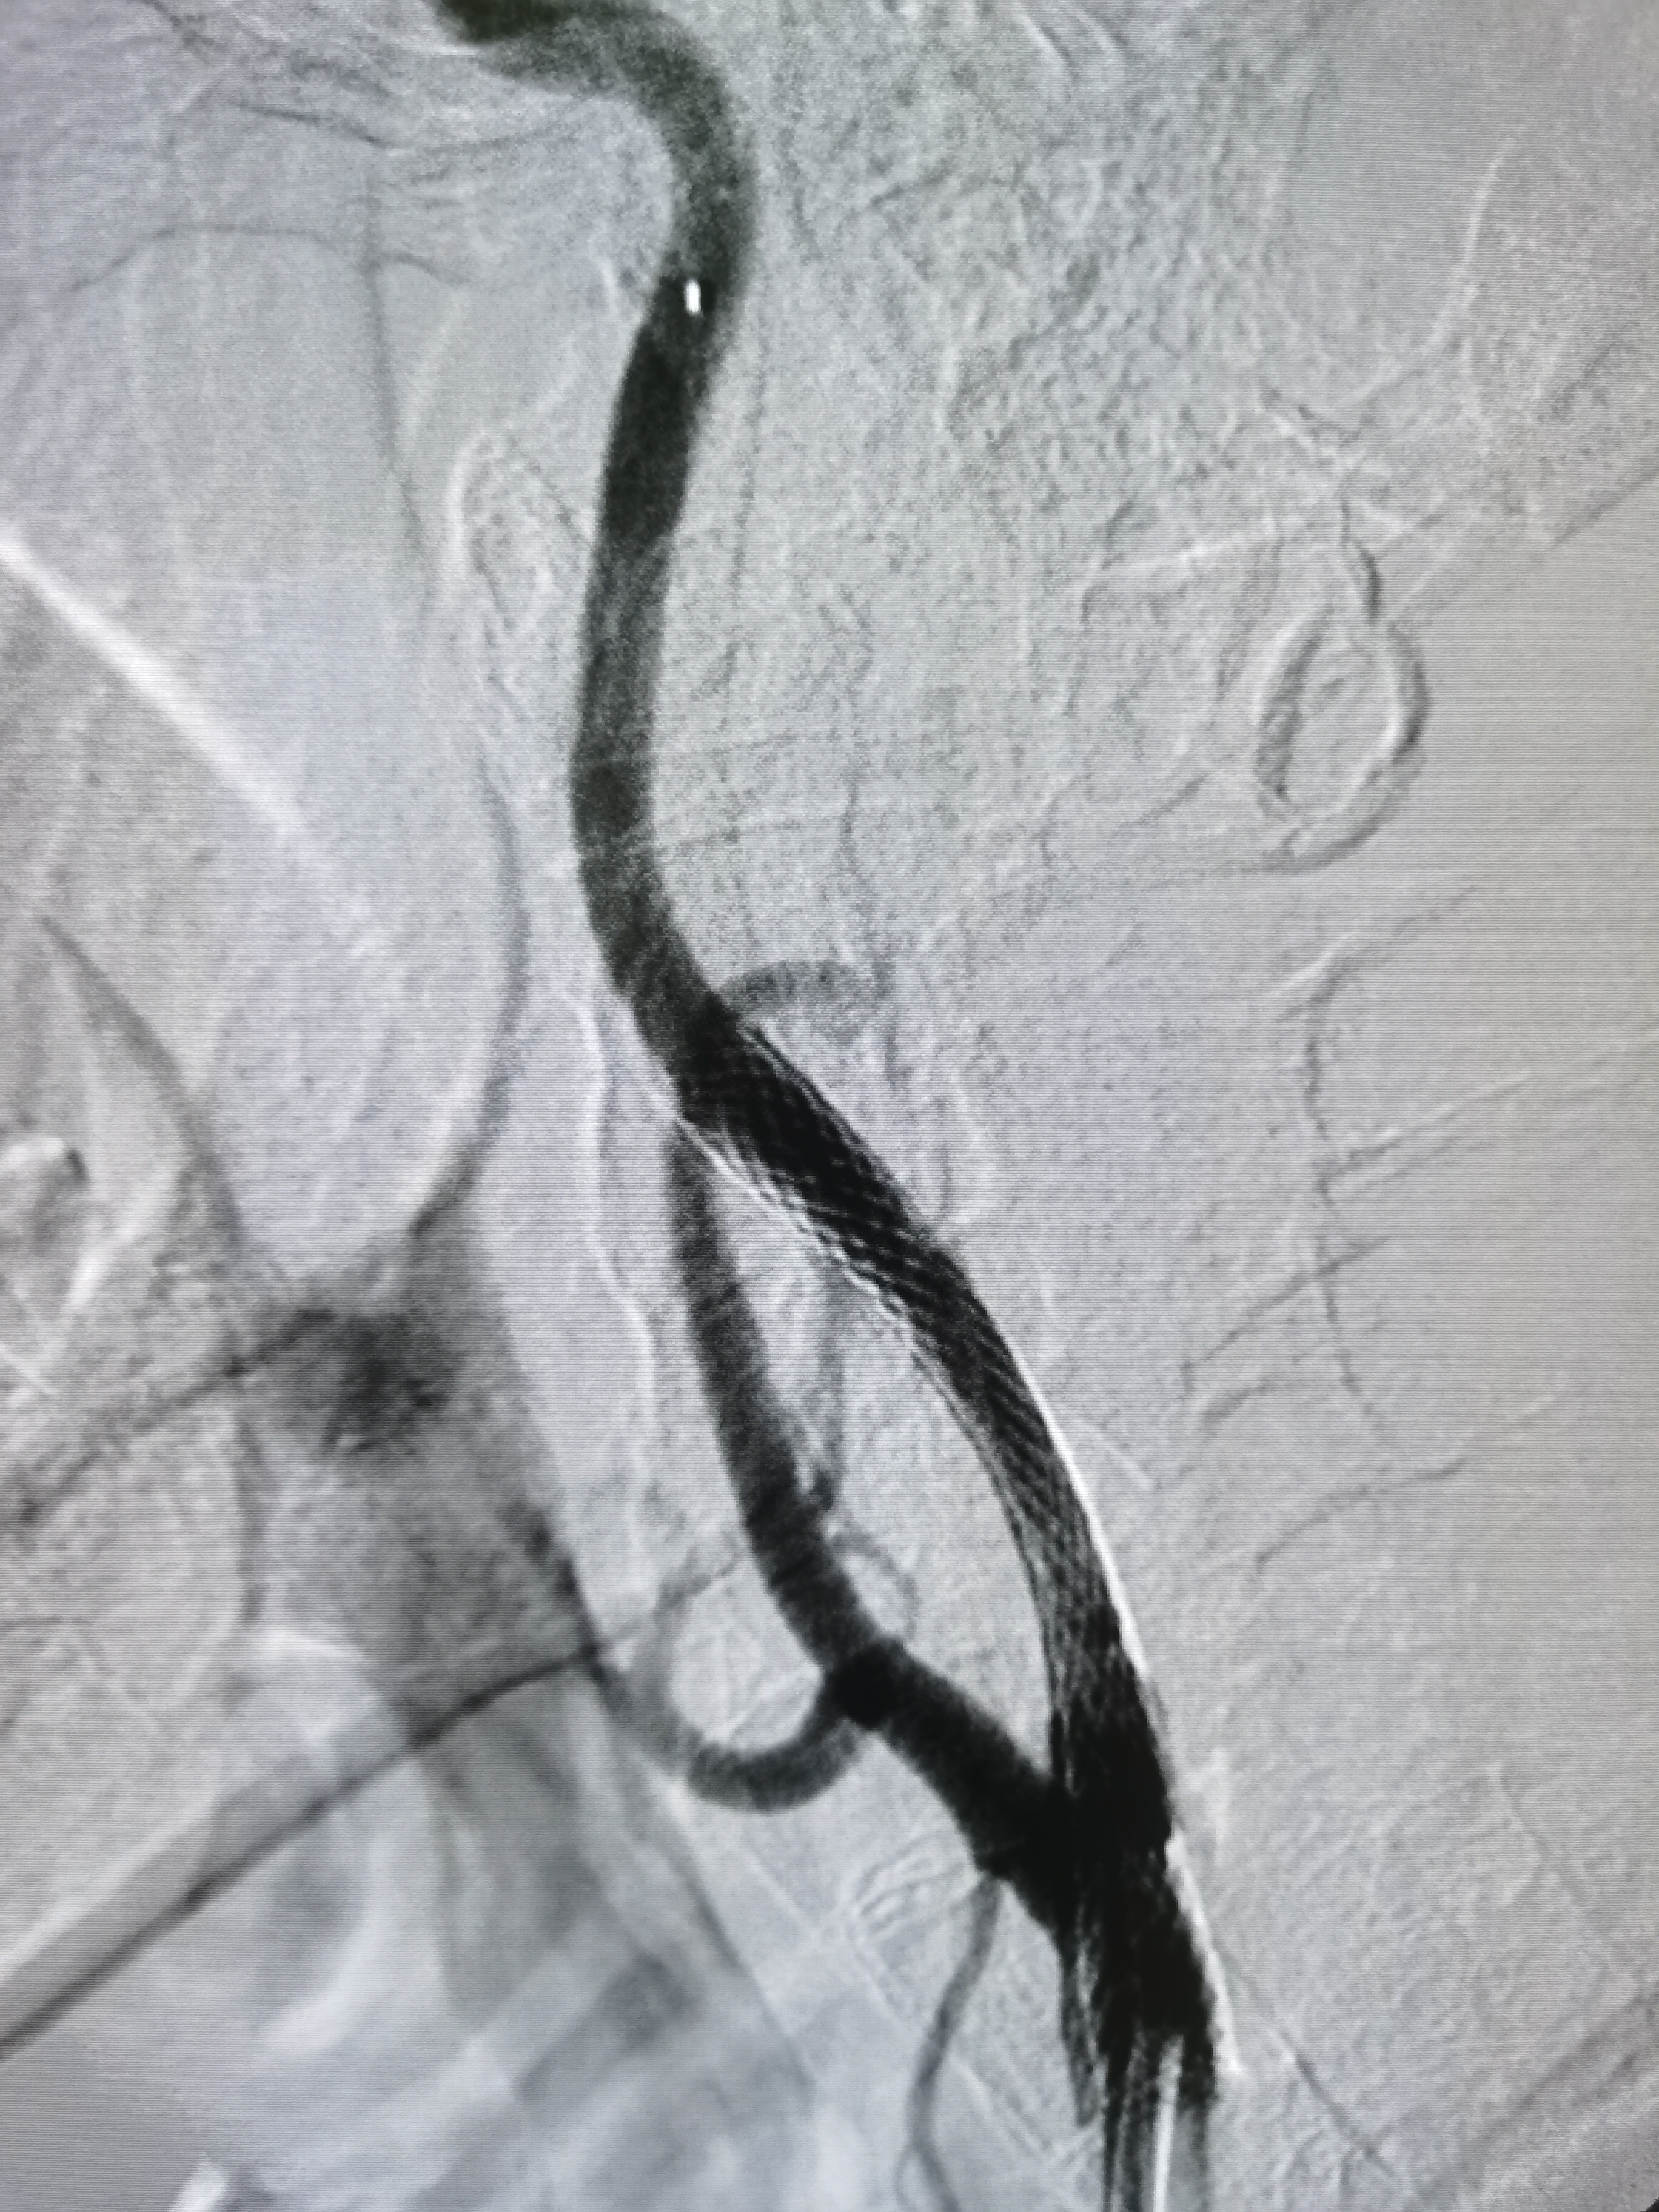

左侧颈内动脉起始部次全闭塞,局部斑块不稳定。

患者造影后明确左侧颈内动脉次全闭塞,斑块不稳定,发生血管急性闭塞风险较大,应积极介入治疗。

8F导引导管到位后明确工作位。